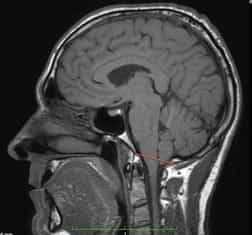

Неврологический осмотр и стандартный перечень неврологических обследований (ЭЭГ, Эхо-ЭГ, РЭГ) не дают специфических данных, позволяющих установить диагноз «аномалия Киари». Как правило, они выявляют лишь признаки значительного повышения внутричерепного давления, т. е. гидроцефалию. Рентгенография черепа выявляет только костные аномалии, которыми может сопровождаться аномалия Киари. Поэтому до внедрения в неврологическую практику томографических методов исследования диагностика этого заболевания представляла для невролога большие затруднения. Теперь врачи имеют возможность поставить таким пациентам точный диагноз.

Следует отметить, что МСКТ и КТ головного мозга при хорошей визуализации костных структур краниовертебрального перехода не позволяют достаточно точно судить о мягкотканных образованиях задней черепной ямки. Поэтому единственным достоверным методом диагностики аномалии Киари на сегодняшний день является магнитно-резонансная томография. Ее проведение требует обездвиженности пациента, поэтому у маленьких детей она проводится в состоянии медикаментозного сна. Кроме МРТ головного мозга для выявления менингоцеле и сирингомиелических кист необходимо также проведение МРТ позвоночника, особенно его шейного и грудного отделов. При этом проведение МРТ исследований должно быть направлено не только на диагностику аномалии Киари, но и на поиск других аномалий развития нервной системы, которые часто с ней сочетаются.

По особенностям симптоматики и на основании осмотра невролога диагноз мальформации Киари поставить невозможно. Энцефалография, исследования сосудов головы тоже не дадут никакой информации касательно причин неврологических нарушений, однако могут показать наличие повышенного давления в черепе. Рентгенография, КТ, МСКТ укажут на наличие дефектов костей черепа, которые характерны для этой патологии, но состояние мягкотканных структур, нервной ткани установить при этом нельзя.

Точная диагностика аномалии стала возможна благодаря использованию МРТ, посредством которой врач может определить и костные пороки, и варианты развития самого мозга, его сосудов, уровень расположения отделов относительно черепных костей, их размеры, объем задней черепной ямки и ширину большого затылочного отверстия. МРТ можно считать единственным точным и самым достоверным методом выявления патологии.

МРТ требует обездвиживания пациента, который должен какое-то время спокойно лежать на столе аппарата. У детей с этим могут возникнуть значительные трудности, поэтому исследование проводят в состоянии медикаментозного сна. Для поиска сочетанных пороков спинного мозга и позвоночника исследуют также эти отделы позвоночного столба.